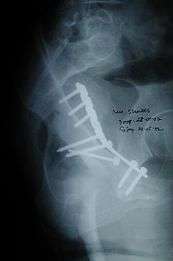

If the fragments do not fall into place, or if there are bone pieces in the joint, or if the joint is unstable, surgical fixation using screw(s) and plate(s) is performed

Post-surgery treatment: depending on the stability achieved, the person may be allowed standing and walking with help of support for about six to eight weeks.

Full function may return in about three months.

Innominate bone is a flat bone with many curves. In most part the bone is thick enough and has broad surfaces that are amenable to primary fixation using lag screw(s) and to neutralize forces across the bone one needs to add plate(s) on the surface of the fractured fragments for it to heal without deformity.

Implants : normally lag screws and reconstruction plates are preferred implants